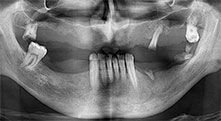

residual dentition

A 40-year-old patient with very poor residual dentition wanted an implant-based restoration. Because he is a smoker, a sinus lift in the maxilla with a fixed denture was contraindicated. A bar denture on four anterior implants was planned.